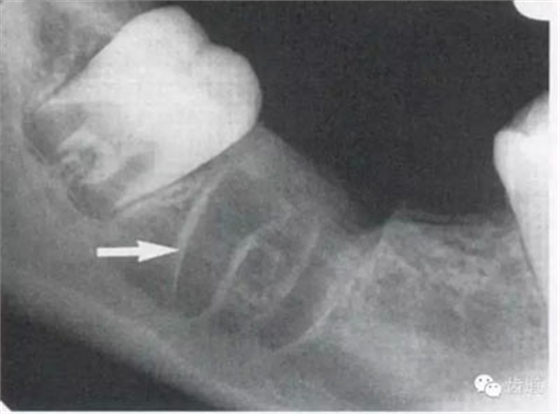

4)外斜線:

由升支前緣下部斜向前下方,為一密度高的帶狀影像。常重疊在第二、三磨牙牙冠處、頸部或根部,使牙髓室或根管不能清晰顯示

5)下頜管:

位于磨牙牙根尖下方,呈寬約為0.4cm凹面向下邊緣整齊的帶狀密度低的影像,其兩側(cè)有密度高的線條狀影像,為下頜管骨密質(zhì)

7)下頜角區(qū):

在下頜管的后下區(qū)域,骨小梁稀少,這是正常骨質(zhì)疏松區(qū)域 8)頦嵴: